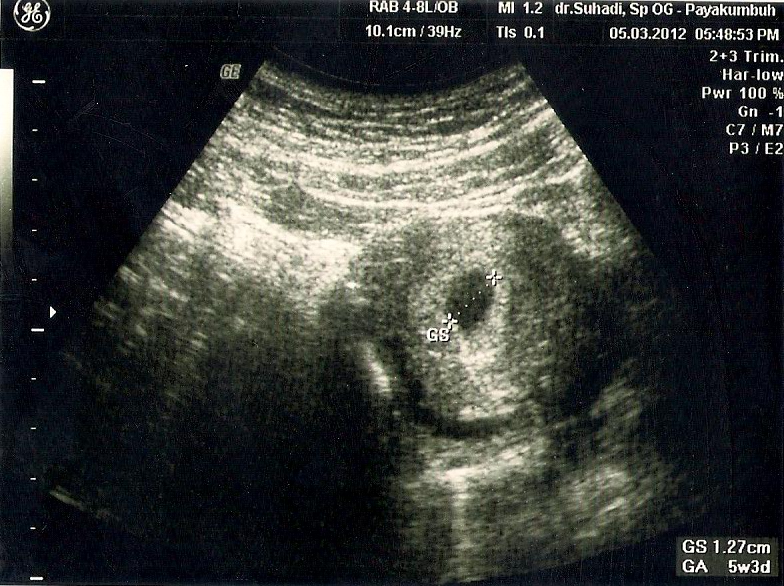

Gambaran Hasil Usg Kehamilan 5 Minggu Yang Perlu Diperhatikan - Hamil.co.id

Gambaran Hasil Usg Kehamilan 5 Minggu Yang Perlu Diperhatikan - Hamil.co.id